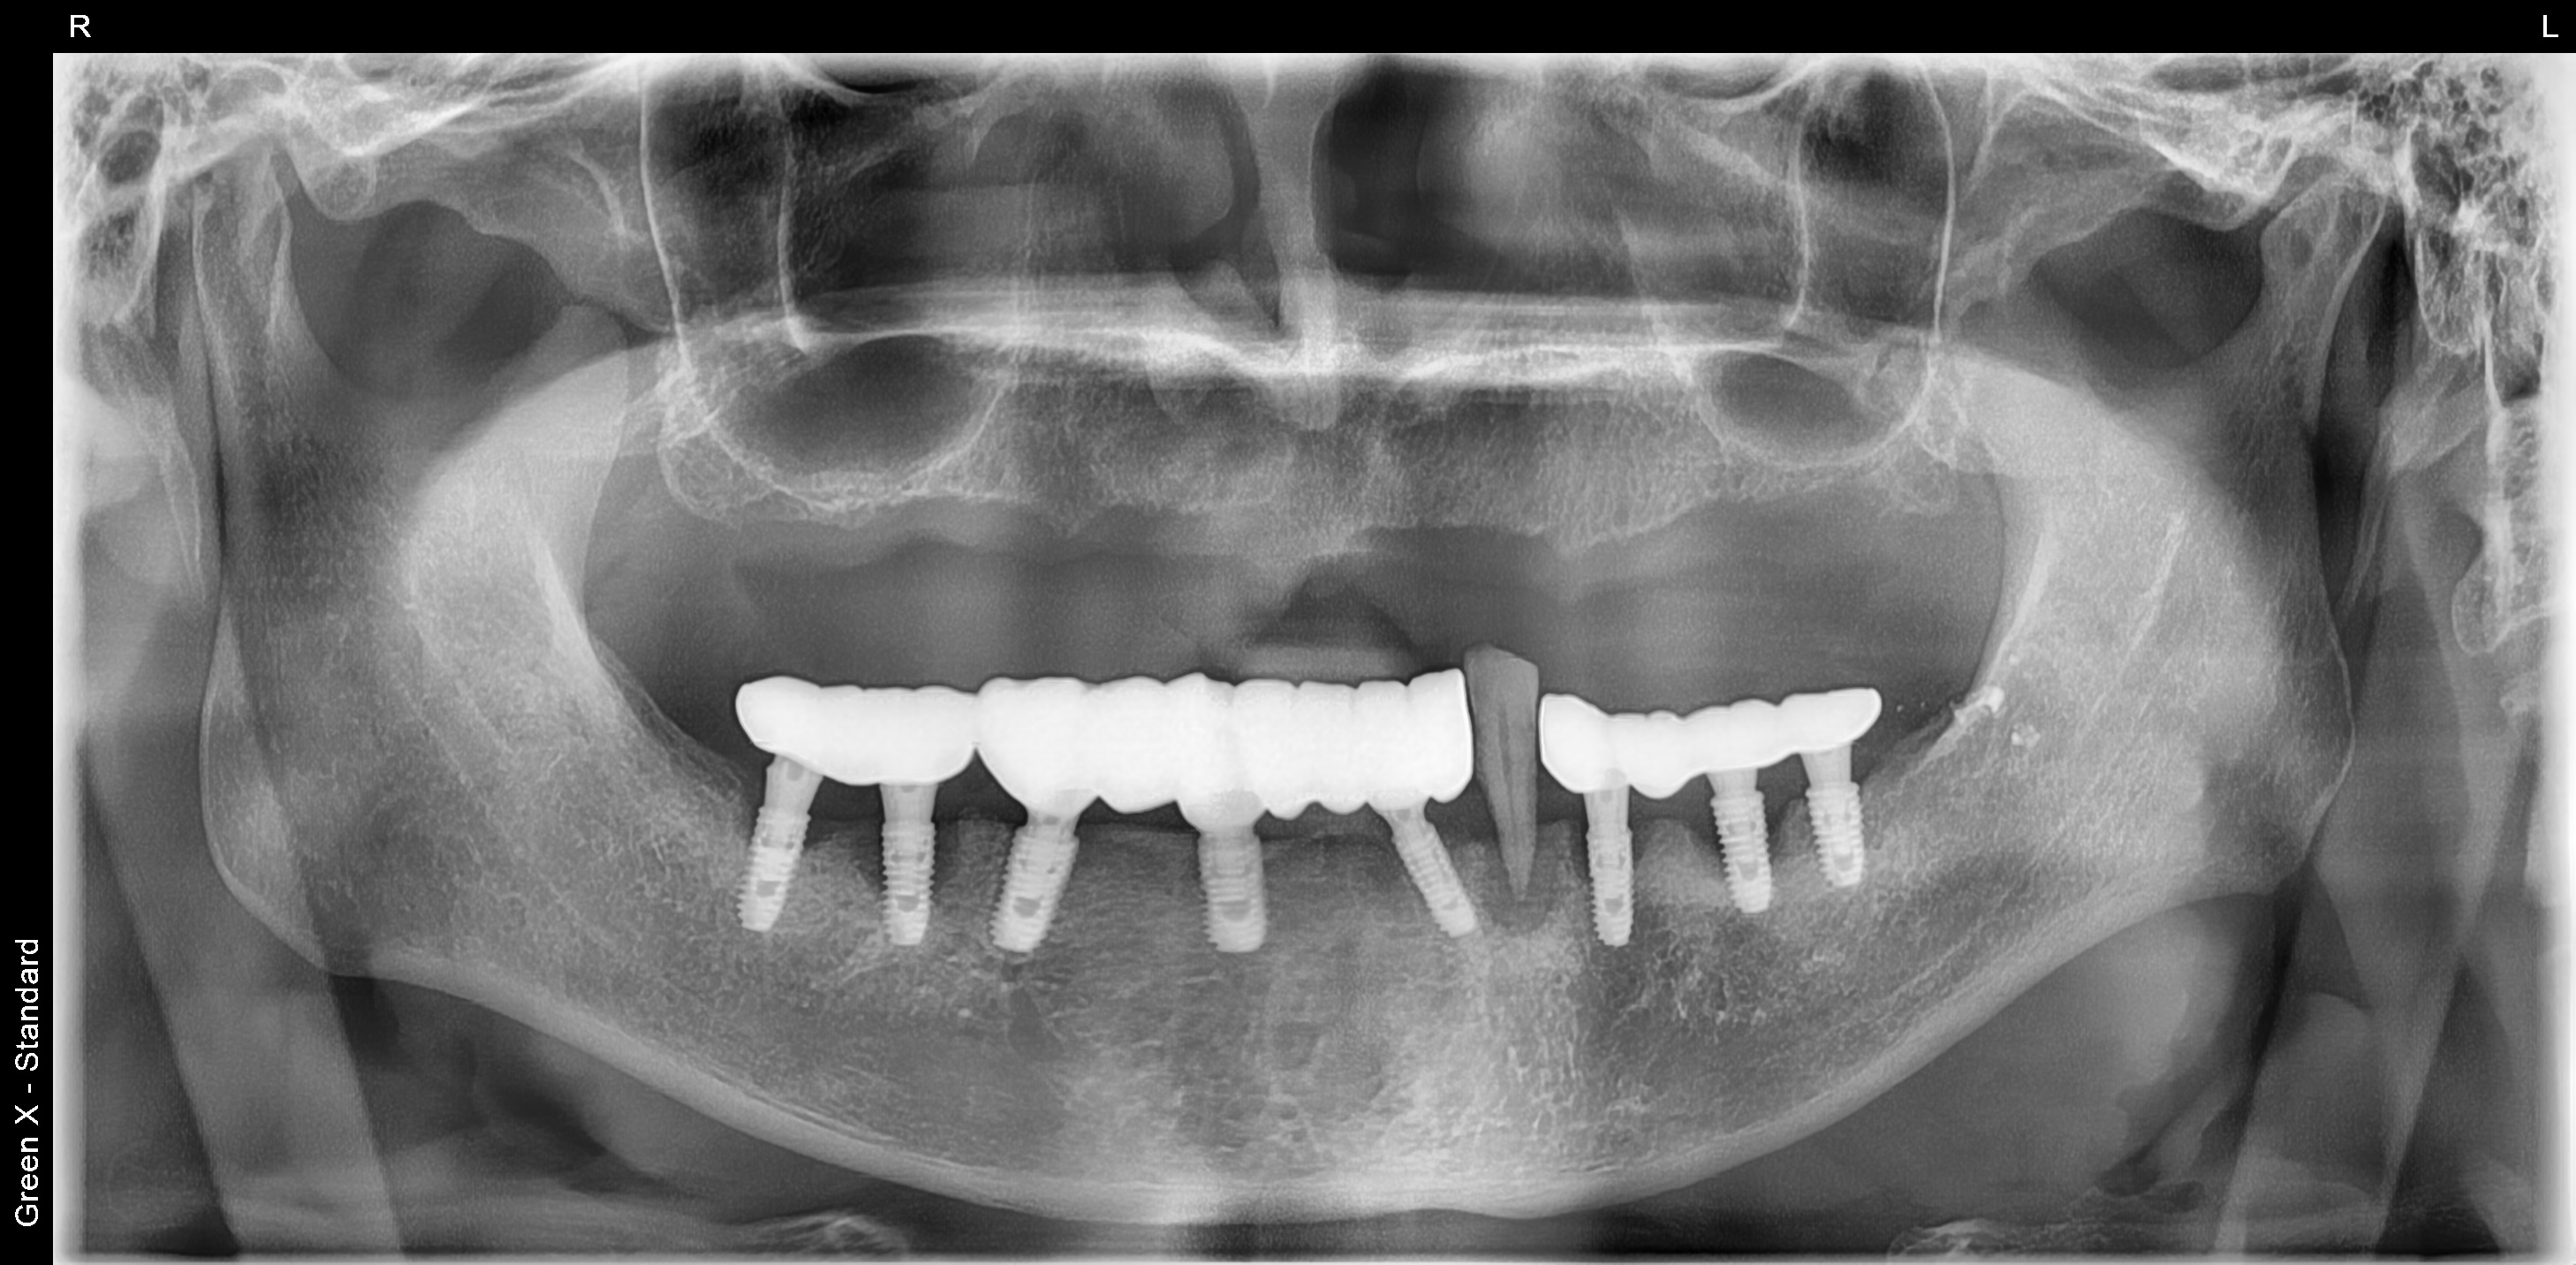

김포 풍무동 서울케이치과 위턱 전체 임플란트 사례

9개 임플란트 식립 후 고정식 보철로 위턱 전체 치아 수복한 사례입니다.

(아래턱 임플란트는 수년 전 타치과에서 식립했으나, 임플란트 주변 치조골이 소실되고 있어 추후 재식립이 필요합니다.)

<치료 후>